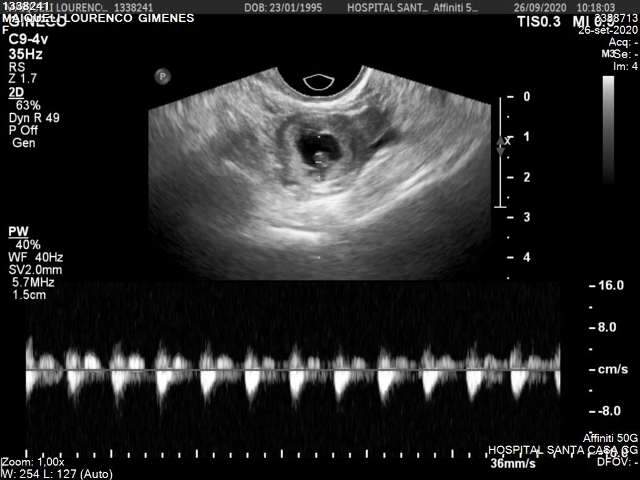

A história começou quando Santos sentiu dores no lado direito do abdômen, o que a levou a procurar atendimento de emergência. Após realizar uma ultrassonografia, os médicos confirmaram que o feto estava do lado direito, o que motivou a internação para cirurgia.

Apesar da cirurgia equivocada, Carina recebeu alta após 48 horas de recuperação. Contudo, 17 dias depois, os sintomas reapareceram, e ela não entendia o que estava acontecendo. Foi então que descobriu que o feto ainda estava se desenvolvendo e já estava com 10 semanas de gestação.

Os médicos precisaram operá-la novamente para retirar a trompa direita, que era a afetada desde o início. Carina, entretanto, não compreendia o que estava se passando, pois acreditava que a trompa já havia sido removida na primeira cirurgia. Buscando explicações, ela solicitou o laudo anatômico ao hospital, onde constava que a amostra retirada da trompa esquerda não era compatível com um diagnóstico de gravidez ectópica.